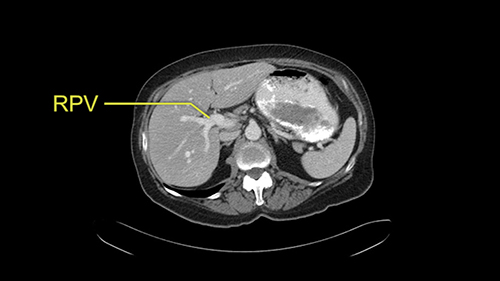

My name is Alice Wei and I’m an associate professor of surgery at the University of Toronto and a hepatobiliary and pancreatic surgical oncologist at the University Health Network. This patient is a 65-year old female who was referred to me with synchronously presenting colorectal liver metastases in Segments 4a, Segment 7, 6 and 5; and I’ve decided to perform a right hemihepatectomy on this patient and in planning this operation there are some procedure-specific and patient-specific slowing down moments.

The procedure-specific slowing down moments from a technical point of view for a right hemihepatectomy include a careful evaluation of the inflow structures including the right hepatic artery, the right portal vein, as well to make sure that I have identified and preserved the left hepatic artery and the left portal vein at all times, and minimize any injury or dissection of the common bile duct. Also, I am careful when I mobilize the right liver, not to tear the right triangular ligament and cause bleeding of the liver as I mobilize it off the retroperitoneum and the bare area. In addition, the last procedure-specific slowing down moment is to carefully identify the right hepatic vein and ensure that I encircle it safely without damaging the IVC or the middle and left hepatic vein structures at all times.

![[RHA]](jpg/preop_sg_moment3.jpg)

The only other most important feature that I usually consider is the portal vein split or the bifurcation, especially if doing a major liver resection like a right lobe. I like to look at the length of the common right portal vein trunk which looks like its probably long enough to put a stapler on. Final decision would be in the OR. If it wasn’t long enough and I was concerned about injuring the bifurcation or the left portal vein, then I would divide the Segment 5-8 and 6-7 portal tracks individually.

![[LPV]](jpg/preop_sg_moment4b.jpg)

This patient has an interesting minor anomaly with what looks like a Segment 7 portal vein coming off close to the bifurcation of the right portal vein but again if I was doing a right lobe which is my plan, this wouldn’t be an issue.